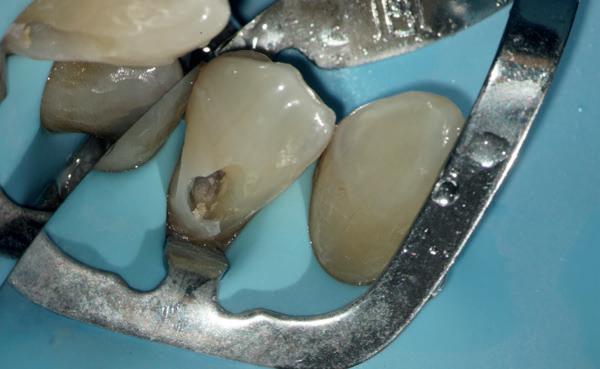

Het uitvoeren van een wortelkanaalbehandeling of een revisie daarvan gaat in veel gevallen gepaard met het vervaardigen van een coronale restauratie. De cariëslaesie is vaak groot of de aanwezige restauratie in het element lekt. Het maken van zo’n coronale restauratie is moeilijk en vergt veel inspanning van de tandarts. De gemodificeerde wigtechniek is een eenvoudige manier om bijna alle complexe en diepe composietrestauraties snel en goed te vervaardigen.

Een lekkende vulling? Geen endo!

De prognose van een wortelkanaalbehandeling wordt in sterke mate beïnvloed door de kwaliteit van de coronale restauratie. Om die reden is het essentieel om de restauratie goed te controleren op kwaliteit en op aanwezigheid van cariëslaesies. Ook bij twijfel is het aan te raden de vulling of kroon te vervangen door een nieuwe composietrestauratie vóórdat er overgegaan wordt tot een endodontische behandeling.

Als er wordt overgegaan tot het maken van een (nieuwe) restauratie, zal het vaak gebeuren dat de preparatiegrens subgingivaal of zelfs ter hoogte van het alveolaire bot uitkomt. Dergelijke situaties ver-

gen een extra inspanning van de algemeen practicus, waarbij de reguliere restauratietechnieken niet afdoende zullen zijn.

De laatste jaren is er gelukkig steeds meer aandacht gekomen voor behoud van moeilijk te restaureren elementen. Chirurgische kroonverlenging, orthodontische extrusie en ‘Deep Margin Elevation’ zijn veelgebruikte methoden om elementen te behoeden voor extractie en hun oorspronkelijke functie terug te geven. Deze methoden zijn complex en vergen chirurgische ervaring. De gemodificeerde wigtechniek is simpel; de uitvoering lijkt op die van de standaard composietrestauratie en is minimaal invasief.

Auteur Tijmen Dusseljee legt hieronder stap-voorstap uit hoe de techniek werkt:

Eerst resto, dan endo!

Pas als het element een mooie coronale afsluiting, contactpunten en functionaliteit heeft, kan er overgegaan worden tot het uitvoeren van een endodontische behandeling. Zo kan er voorspelbaar gewerkt worden en kan het element een geruime tijd na de wortelkanaalbehandeling goed worden geëvalueerd.